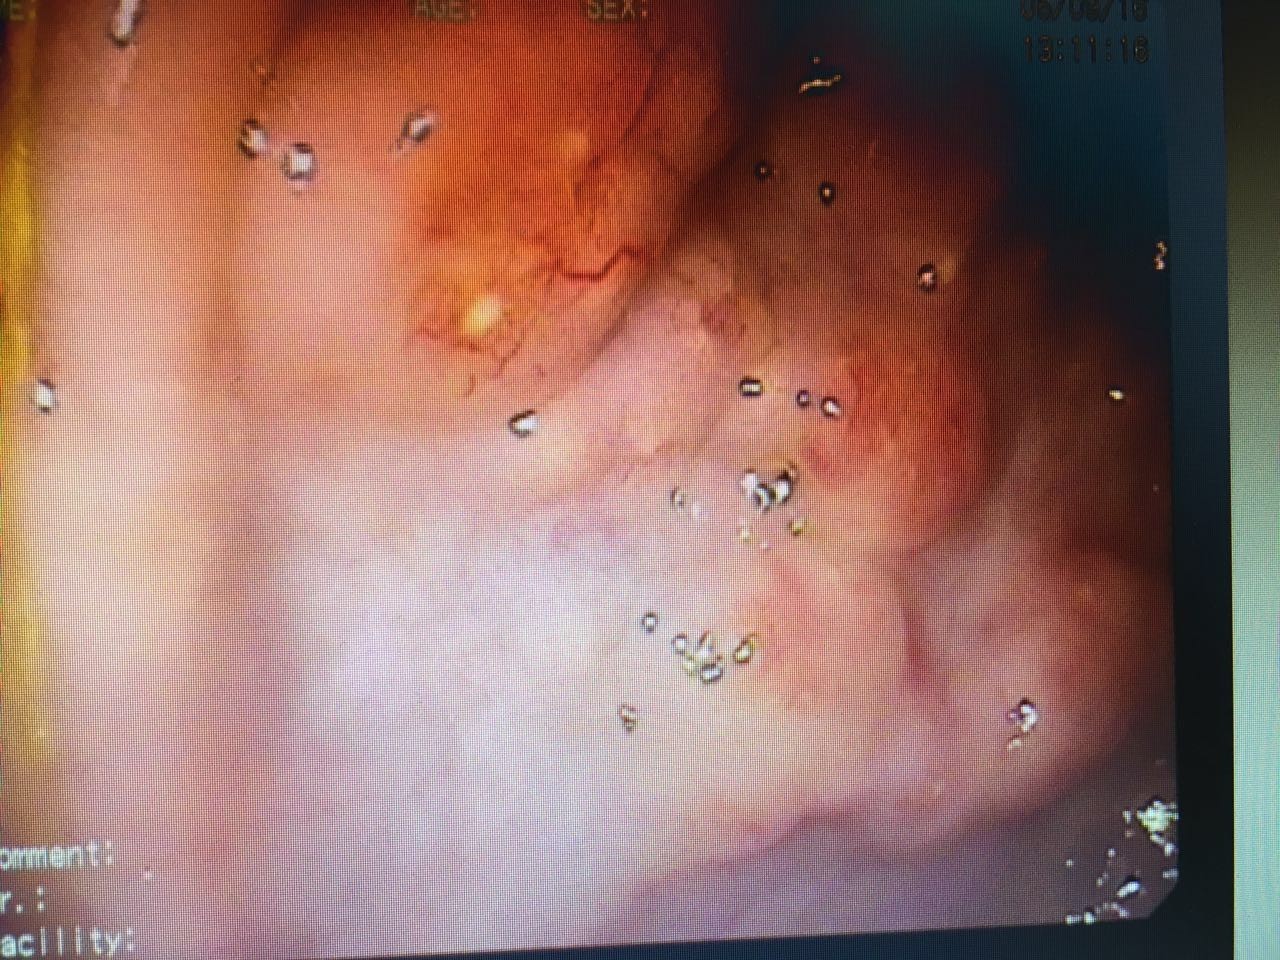

抗生素使用后的第三天,热型基本上没有变化,还是午后高热。只不过病人食欲好转了,咳嗽有点减轻,大便次数减少……四环素已经使用了4次,*虫病恙**可以不考虑了;目前结合患者超高的嗜酸细胞,血吸虫血清学反应阳性(大便孵化结果还没有拿到),开始按血吸虫病给予吡喹酮治疗。吡喹酮治疗后24小时,体温最高峰由39度降低到38度,咳嗽消失。从治疗反应来说,比较符合血吸虫感染了,但是患者的体温能够完全降至正常吗?肺部改变一定是血吸虫所致吗?毕竟就已知的血吸虫相关知识而言,血吸虫主要还是寄生在门静脉系统,然后还是在肠系膜下静脉和直肠上静脉产卵……书本有提过血吸虫的肺部改变为间质性改变,因为相对少见而且缺乏具体的表述。毕竟大部分研究血吸虫的文献资料还是在90年代,肺部CT没有普及的时候。根据目前患者的情况,比较可行的确诊手段一个是等大便孵化出尾蚴,还有就是我们消化科先安排肠镜检查看看。结果肠镜做下来,确实有点意思。不仅有我们常见的粘膜表面黄色点状颗粒(聚集成团的血吸虫虫卵)沉着,还有无数个丘疹样隆起(图4),活检了3块。看见这样的表现,我们心里已经基本有数了,回来立刻停了抗生素。在等待病理结果的过程中,患者体温慢慢的降至正常。吡喹酮治疗第六天,患者突然出现肌肉酸痛,一过性皮疹(可惜当时患者不在医院里边,我们没有看见患者也没有拍照),我们考虑为类赫氏反应,给予了激素,次日不适消失。最后肠镜病理回来:见图片5。同时血吸虫防治站的结果也回来了:大便孵化出较多尾蚴。急性血吸虫病得以确诊。

图4